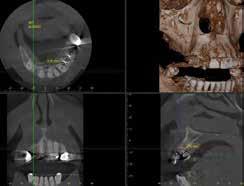

Digital Implant Planning

The implant surgeon should review the entire volume of the CBCT to get acquainted with patient-specific local anatomy and look for bone abnormalities and/or presence of any other pathology. If implants in the mandible are placed, the inferior alveolar nerve should be marked in the volume by identifying its course distal from the mental foramen.

Likewise, in the maxilla, the position of unusually prominent neurovascular bundles in the bone should be marked (Fig. 5).

The next step is to determine the appropriately sized implant from the collection of implants in the chosen implant system. The available bone for implant placement provides the possible size for an implant at a given site and often dictates which implant size can be placed. To measure available bone accurately, the sectional views must be lined up so that the buccolingual and mesiodistal sections are perpendicular to t

the bone surfaces and the view is centered on each implant site (Fig. 6).

Each implant must also meet the following requirements:

l At least 2.65 mm superior to the inferior alveolar nerve 19 and 5 mm mesial to the mental foramen. 20

l At least 1.0 mm (platform-switched implants) to 1.5 mm (nonplatform switched implants) from the implant platform to adjacent teeth21 and at least 3.0 mm between adjacent implant platforms.22

l A 2 mm thick shield of facial bone to the facial implant surface is advised.23

Most implants with completely rough surfaces need to be placed with the implant platform flush or slightly apical to the crestal bone. Placing implants with machined collars apical to the crestal bone may result in bone loss. These requirements typically provide maximum implant dimensions for the available bone. However, available implant dimensions and restorative design considerations including desired emergence profile and support may dictate different dimensions. For example, even if a posterior maxilla implant site features a 12 mm-wide ridge allowing placement of an 8 mm-wide implant, the largest implant size available from a given manufacturer may only be 6 mm in diameter.24 Likewise, if available bone is less than required for restorative needs, site development procedures such as ridge augmentation need to be done.25 Short implants (less than 10 mm length) may help overcome limitations in available bone height, although concerns have been raised about possible mechanical disadvantages from a poor crown implant ratio. Yet, crown implant ratio does not seem to be associated with enhanced peri-implant bone loss and may not affect implant survival.26,27 Small diameter implants (less than 3.5 mm) may have similar bone loss and survival rates than standard diameter implants28 when placed in atrophic ridges, but may have higher complication rates and potential for fracture if placed in posterior areas.29,30